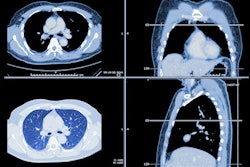

(A) Coronal chest CT shows bilateral lower lobe pleural-based mild reticular opacities with traction bronchiectasis (arrows). (B) Chest radiograph shows subtle corresponding subpleural opacities in basal lung zone bilaterally (arrows). Only one of six readers detected reticular opacity when interpreting radiograph alone. (C) Abnormalities annotated on deep-learning algorithm in basal lung bilaterally with probability of 0.99. Algorithm deemed true-positive for reticular opacity. Five of six readers detected reticular opacity using the algorithm. Image and caption courtesy of the American Journal of Roentgenology.In another interesting result, the radiology residents produced higher sensitivity (97.6%) and accuracy (96.7%) than the board-certified radiologists (90% sensitivity and 94.4% accuracy) when all were using the AI software. All differences were statistically significant (p < 0.001 and p = 0.006, respectively).